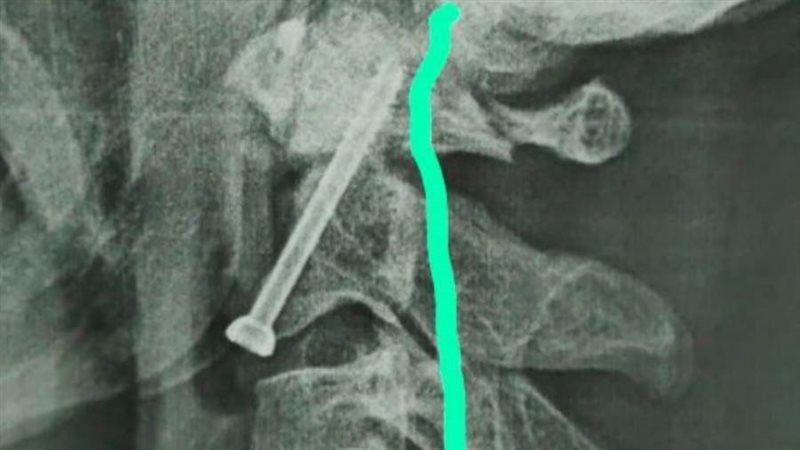

واوضح الدكتور حمدي سعد مدير المستشفى الجامعي انه بعد اجراء الفحوصات والاشاعات اللازمة للمريض تبين وجود كسر في الفقرة الثانية من العمود الفقري الرقبي، ويحتاج إلى جراحة عاجلة لتثبيت الفقرة العنقية، حيث كان هذا الكسر يشكل خطراً كبيراً على النخاع الشوكي وحياه المريض.

وذكر الدكتور عبدالرحمن الشيخ رئيس قسم جراحة العظام انه بعد دراسة الحالة في ضوء نتائج الفحوصات الطبية، تم اتخاذ كافة التدابير التحضيرية للعملية، لافتاً الي ان الفريق الطبي الذي إجري العملية الجراحية للمريض كان تحت اشراف الدكتور أحمد صالح أستاذ جراحة العظام والعمود الفقري، حيث تم تثبيت الكسر بنجاح، و بدأ المريض الحركة بحرية تامة بمفرده بدون اي وسائل مساعدة.